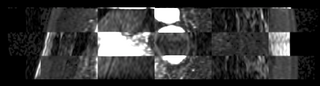

We then align the MRA and DE-MRI images of the same patient, which allows us to transfer the left atrium segmentation using the resulting deformation field. This is shown in the following figures.

Mdepa MRA MDE registration.png Mdepa MDE la segmentation.png